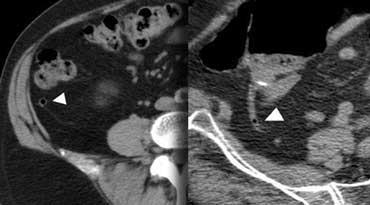

Ruột thừa viêm trên CT. Ruột thừa (mũi tên) chứa đầy dịch và giãn, kèm theo dấu hiệu mờ mỡ quanh ruột thừa (fat-stranding).

CT mô tả ruột thừa viêm là một cấu trúc hình ống tận cùng mù, chứa đầy dịch, được bao quanh bởi dấu hiệu mờ mỡ (fat-stranding).

Trong trường hợp ở bên trái, thành ruột thừa tăng tỷ trọng được ghi nhận trên CT có thuốc cản quang.

Ở những bệnh nhân thiếu mỡ trong ổ bụng, việc sử dụng thuốc cản quang tiêm tĩnh mạch có thể hữu ích trong việc phát hiện ruột thừa viêm.

Viêm túi thừa sigma không biến chứng. Dấu hiệu mờ mỡ và dày thành đại tràng khu trú tại vùng có túi thừa. Không có hình thành áp xe.

Các biến chứng của viêm túi thừa như hình thành áp xe hoặc thủng, có thể được loại trừ tốt nhất bằng CT.

TRÁI: Viêm túi thừa sigma. Túi thừa (mũi tên) được bao quanh bởi lớp mỡ tăng tỷ trọng. Thành sigma dày. PHẢI: Ung thư sigma với dấu hiệu mờ mỡ giới hạn.